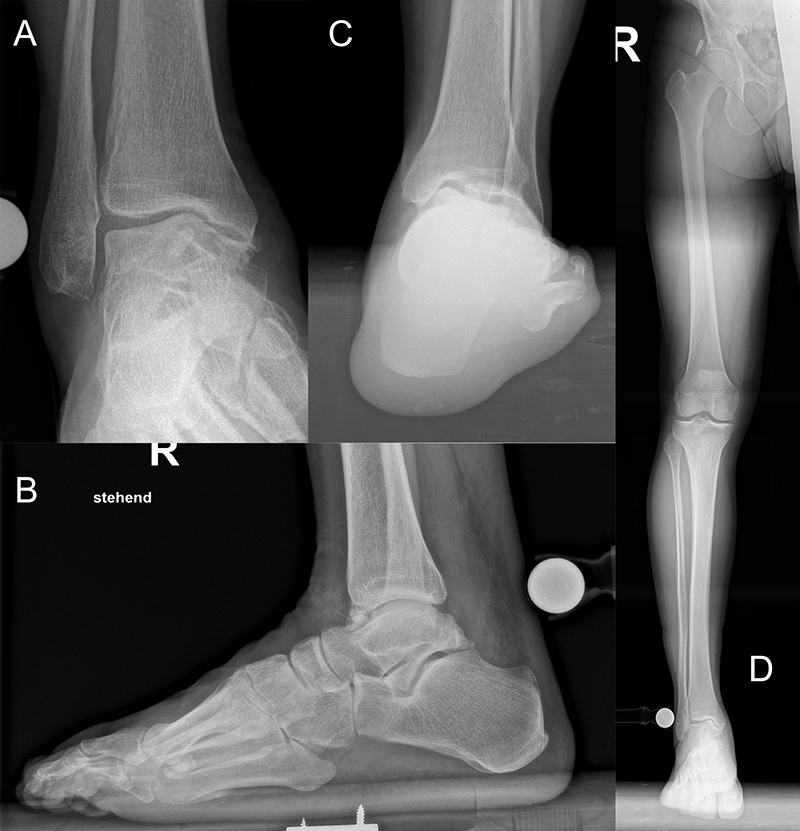

Native Röntgenaufnahmen des Sprunggelenks in 2 Ebenen unter Belastung (antero-posterior und lateral) erlauben Gelenkspaltverschmälerung, osteophytäre Anbauten sowie Achsfehlstellungen zu beurteilen. Eine „Canale-Aufnahme“ (Pronation des Fußes von ca. 15 °, Röntgenstrahl 75 ° nach kranial) 9 kann hilfreich sein, die subchondralen Oberflächen einzusehen. Die korrekte Abbildung der Sprunggelenkgabel in der sogenannten „Gabel-Aufnahme“ (mortise-view) ist zudem notwendig zur Beurteilung der Gelenkkongruenz. An Grenzen stößt die konventionelle Röntgenaufnahme allerdings bei OCLs ohne weitere knöcherne Veränderungen. Bis zu 50% der OCLs sind auf konventionellen Röntgenaufnahmen nicht sichtbar. Auch kann der Zustand des Knorpels nicht beurteilt werden 10. Bei Achsfehlstellungen werden zusätzlich Rückfußachs-Aufnahmen (Saltzman View) angefertigt bzw. eine Einbeinstandaufnahme zur Bestimmung der Becken-Bein-Achse.

Zur Vollansicht und zum Lesen der Bildbeschreibung bitte das Bild anklicken.